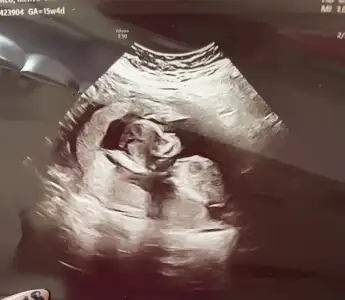

Kızlar selam kontrolden çıktım her şey yolunda çok şükür 15+4 kısa kısa ben de bahsedilenlere ben de cevap vereyim;

Son olarak yakışıklı oğlumu bırakıyorum buraya teyzeleri, hepinizi öpücükler🤍

Oyy maşallah canım profilden ne kadar güzel yüz hatları çok belirgin masallah :KK68:

maşallah canımmm sağlıkla gelsin inşallah 😍😍